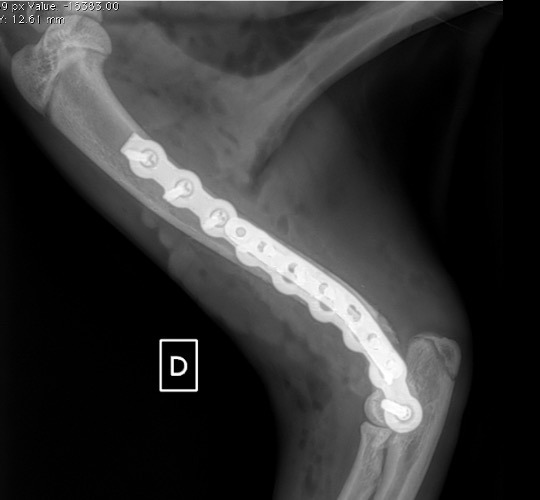

Notre préférence va vers le placement de deux plaques humérales : une médiale de la plus grande taille possible et l’autre latérale, généralement d’une taille inférieure à la première. Dans l’exemple 1 (chat européen), une plaque de 2 mm est utilisée médialement et une plaque de 1,5 mm latéralement. Dans l’exemple 2 (chien Malinois), une plaque de 3,5 mm est utilisée médialement et une plaque de 2,7 mm latéralement.

Exemple 1 :

Figure 1 : Pré-op

Figure 2 : Post-Op Immédiat

Figure 3 : Post-Op 1 Mois

Figure 3 : Post-Op 2 Mois